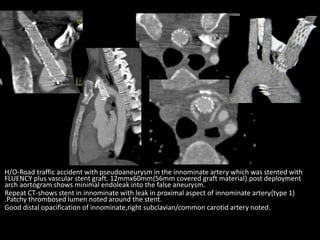

H/O-Road traffic accident with pseudoaneurysm in the innominate artery which was stented with

FLUENCY plus vascular stent graft. 12mmx60mm{56mm covered graft material}.post deployment

arch aortogram shows minimal endoleak into the false aneurysm.

Repeat CT-shows stent in innominate with leak in proximal aspect of innominate artery{type 1}

.Patchy thrombosed lumen noted around the stent.

Good distal opacification of innominate,right subclavian/common carotid artery noted.

H/O-Road traffic accidentwith pseudoaneurysm in the innominate artery which was stented with FLUENCY plus vascular stent graft. 12mmx60mm{56mm covered graft material}.post deployment arch aortogram shows minimal endoleak into the false aneurysm. Repeat CT-shows stent in innominate with leak in proximal aspect of innominate artery{type 1} .Patchy thrombosed lumen noted around the stent. Good distal opacification of innominate,right subclavian/common carotid artery noted.